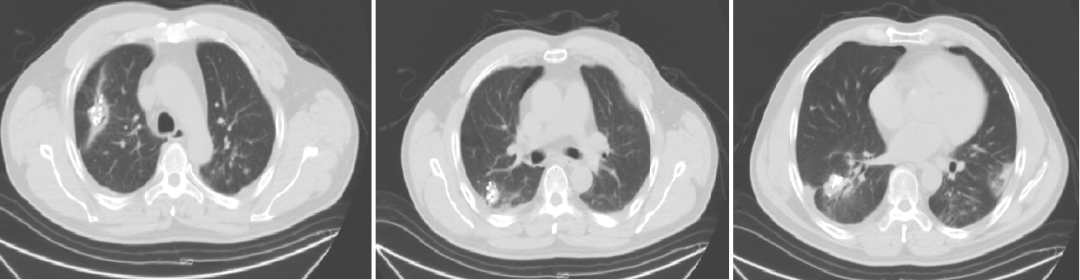

2020-1-7强化CT(我院)

入院诊断:直肠(上段)中分化腺癌;cT0N0M1,IV期;双肺转移;MSS型,RAS/BRAF基因野生型;ERBB2基因扩增型。

2020-1-8至2020-3-4 行4周期西妥昔单抗+FOLFIRI方案治疗,第2周期起联合曲妥珠单抗治疗。

2020-3-23至2020-7-28 予5周期贝伐珠单抗+曲妥珠单抗+伊立替康+卡培他滨(因菌血症输液港取出换用卡培他滨,因皮疹反应不耐受换用贝伐珠单抗)。

二线治疗疗效评价:部分缩小,SD。

维持治疗

2020-8-19至2020-10-22 予4周期维持治疗:贝伐珠单抗+曲妥珠单抗+卡培他滨。

维持治疗疗效评价:部分略大,SD。

局部治疗(二):SBRT治疗

2020-11-6至2020-11-25 左肺下叶及右肺下叶转移灶放疗:95% PTV1-2 74.7Gy/4.98Gy/15F。

2020-12-31至2021-1-19右肺上叶转移灶放疗:95% PTV 74.7Gy/4.98Gy/15F。

SBRT疗效评价:部分缩小。